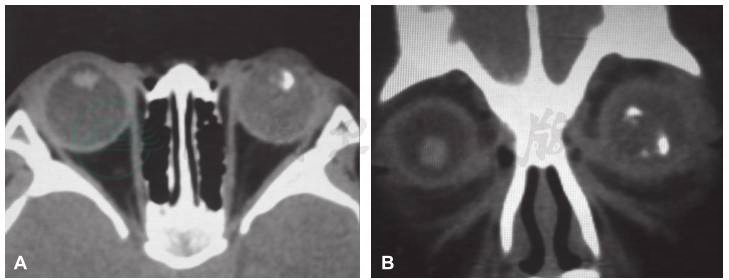

术后病理组织学检查结果显示左眼畸胎瘤样髓上皮瘤,肿瘤细胞生长活跃(图3)。肿瘤主要位于虹膜后的前玻璃体腔,视盘、筛板、筛板后视神经及视神经切除断端均未见明显肿瘤组织侵犯,肿瘤组织附近可见虹膜、睫状体色素上皮呈瘤样增生,并见软骨组织和纤维结缔组织增生,虹膜表面机化膜形成,虹膜周边粘连,继发视网膜脱离及视网膜下可见渗出。肿瘤组织行免疫组织化学染色检测显示:S-100(+),CD56(+),NSE(-),Syn(-),GFAP(-),Vimentin(-),Ki-67(-),Bcl-2(-),Melan-A(-),HMB45(+)(图4)。最终诊断为左眼畸胎瘤样髓上皮瘤。患儿术后1周出院,建议到儿科会诊,密切随访至今,病情稳定未见复发(图5)。

图4 左眼畸胎瘤样髓上皮瘤免疫组织化学染色S-100阳性(DAB,100×)

髓上皮瘤的发病年龄较小,一般在5岁以内。该病多为单眼发病,极少有双眼发病者。眼内髓上皮瘤常以白瞳症、斜视、视力下降或眼痛就诊,因肿瘤常发生在睫状体区域,易继发青光眼。新生睫状体假膜是髓上皮瘤的特征性表现。这层假膜是由肿瘤细胞移行于晶状体后表面产生的一层胶原组织构成。MRI及UBM对诊断该病有一定的价值。髓上皮瘤的临床表现与视网膜母细胞瘤相类似,两者的鉴别诊断较为困难,导致病理诊断是鉴别两者的金标准。本例患儿的病理特征为肿瘤细胞生长活跃,肿瘤组织免疫组织化学检测S-100阳性。S-100为神经组织标志物,存在于神经组织,垂体、颈动脉体,肾上腺髓质、唾液腺、少数间叶组织内,常用于神经鞘瘤、恶性黑色素瘤、脂肪肉瘤、软骨肿瘤诊断等。结合病理组织学改变和免疫染色结果,本例患儿最终诊断为畸胎瘤样髓上皮瘤。